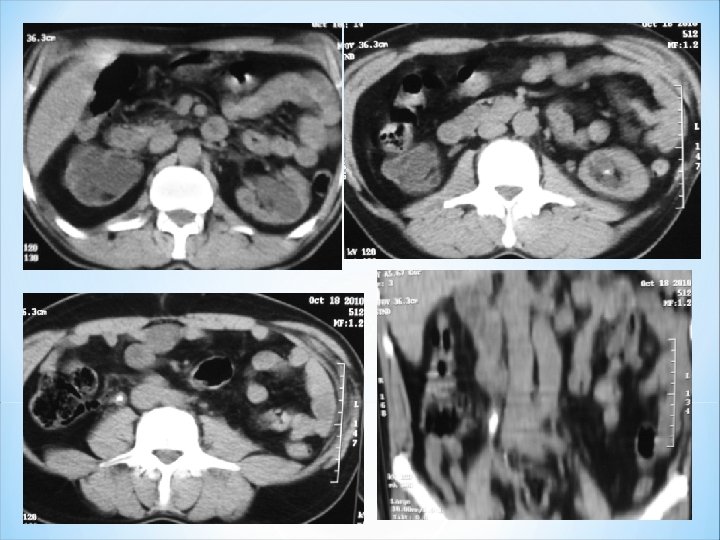

Évaluation après pose d’une sonde JJ en post-lithotritie extracorporelle (LEC). Coupe axiale: calcul se dégage de la sonde JJ. Reconstruction 2 D courbe frontale: calcul résiduel autour de la sonde.

Contrôle TDM après LEC: -c: Hématome avec brèche parenchymateuse et persistance d’un minime calcul dans un groupe caliciel moyen non dilaté. +c: Hématome antérieur + contusion rénale. Contenu dense des cavités excrétrices.